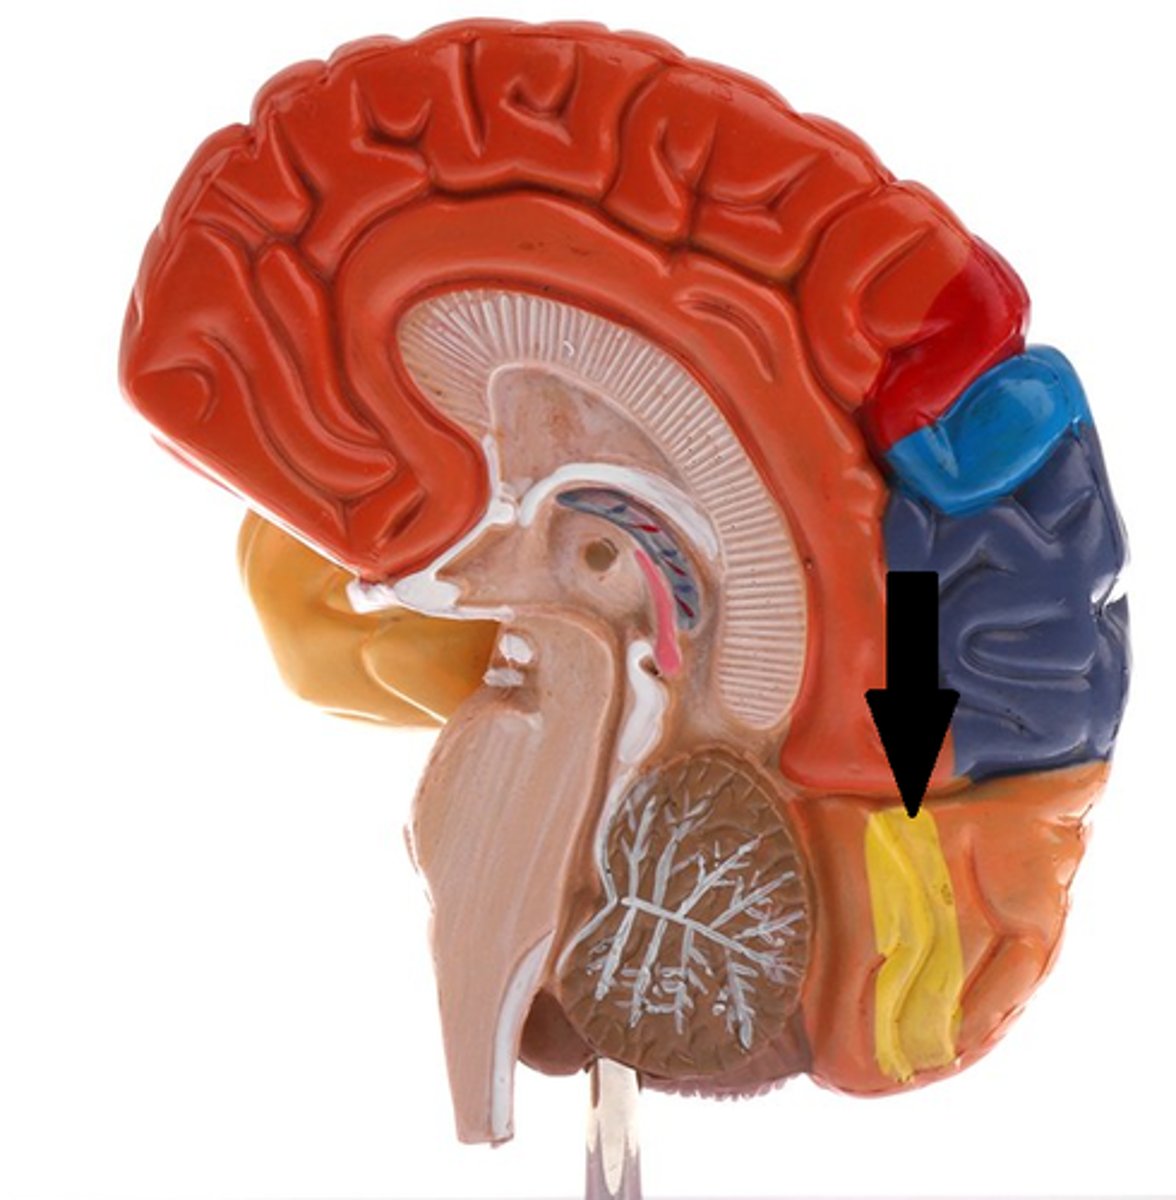

parietal lobe

occipital lobe

Primary visual cortex

Primary auditory cortex

Primary fissure